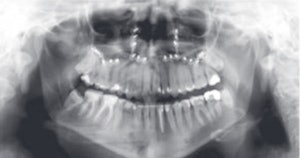

An example of cone-beam CT. In this instance, the lower left third molar (d. 38) was imaged after panoramic radiograph with CBCT. The arrows mark the mandibular canal. Images courtesy of Dr. Anni Suomalainen.